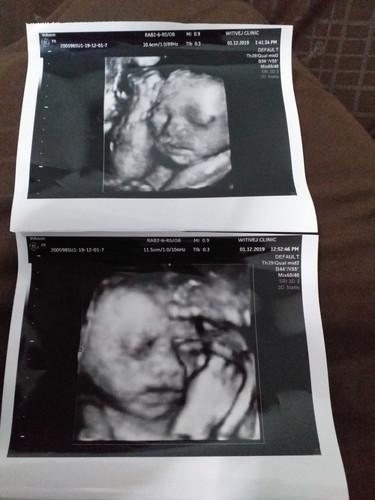

อัลตราซาวด์ 4 D

29 week ได้ลูกสาวสมใจเลยจร้าบ้านนี้ กำหนดคลอด 12 ก.พ.63 เเม่ๆบ้านไหนกำหนดคลอดเดือนก.พ. ได้ลูก ญ. หรือ ช. มาโชว์หน่อยคร้า คุนพ่อบ้านนี้ตื่นเต้นมาก เพราะหน้าเหมือนคุนพ่อ เเต่ปากกับจมูกได้เเม่ ดีใจสุดๆเลยจร้า

อัลตราซาวด์ 4 D 2000 จร้า วิธิเวชคลินิก ไทรน้อย จ.นนทบุรีจร้า